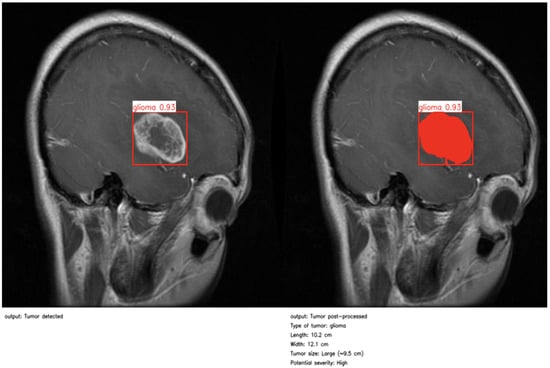

As illustrated in Figure 4 and Figure 5, the proposed method enables precise post-detection analysis. For instance, a pituitary macroadenoma, detected with a high confidence score (0.92), exhibits a computed area of 16.27 cm2, corresponding to a large and clinically significant lesion. Similarly, a glioma lesion identified with 0.93 confidence yields dimensions of 10.2 × 12.1 cm and an estimated size of 9.5 cm2, indicative of aggressive growth potential. Notably, the contrast-enhanced pipeline enables the detection of peripheral hyperintense foci—small white patches within the ROI—which may correspond to early infiltrative zones or satellite tumor loci. These critical features are often indistinguishable in raw YOLO segmentation, highlighting the added diagnostic value of our approach.

Figure 4. First example of post-processing and clinical report.